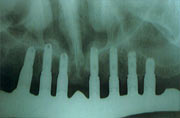

| 初診時 | 下顎に適用されたOIB及び上顎総義歯 |

| 上下顎に適用されたOIB | 上顎に埋入されたフィクスチャー |